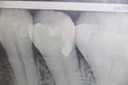

Frank Fukuda #30 pre-op

Frank Fukuda #30 caries removal